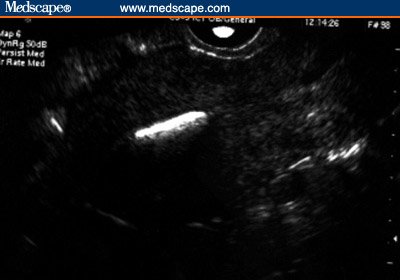

Figure 1. Sonographic appearance of the LNG-IUS. Sagittal view of the

uterus: the proximal and distal ends of the vertical arm of the device, in

the internal cervical os and the fundal region, respectively (arrows).